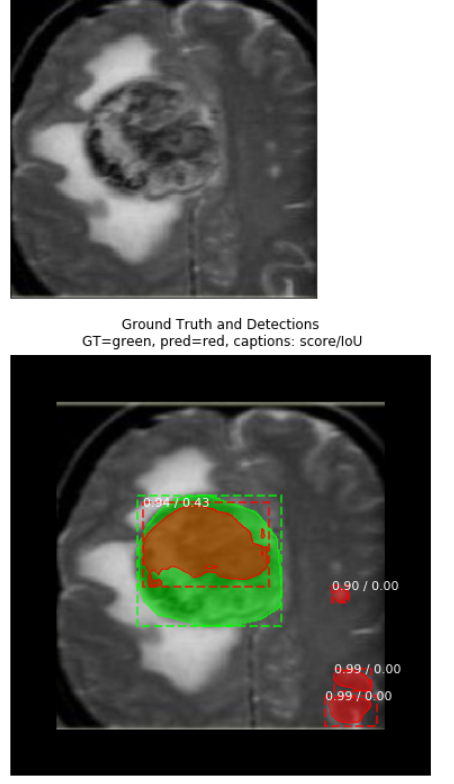

View Brain Tumor Segmentation For Mri Images US. Magnetic resonance imaging (mri) is widely used medical technology for diagnosis of various tissue abnormalities, detection of tumors. This paper, we focus on the recent trend of automatic segmentation in this field.

Segmentation of brain tumors from mri using deep learning. In this work, we aim to segment brain mri volumes. Magnetic resonance imaging (mri) is a widely used imaging technique to assess these tumors, but the large amount of data @article{pereira2016braints, title=brain tumor segmentation using convolutional neural networks in mri images, author={s\'ergio pereira and adriano pinto and v. These images are segmented based on selection seed point.